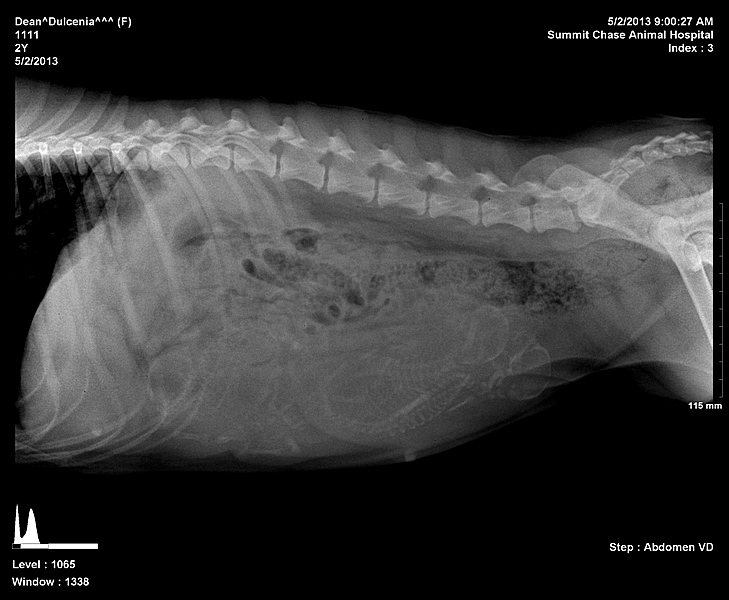

Dulcie xrays preg 1